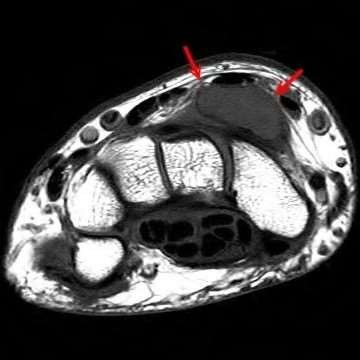

Question 6

A 22-year-old male falls onto an outstretched hand and sustains a displaced fracture through the proximal pole of the scaphoid. Avascular necrosis of the proximal pole is highly likely due to the disruption of its primary vascular supply. Which vessel provides this critical retrograde perfusion?

Explanation

The primary blood supply to the scaphoid is from the dorsal carpal branch of the radial artery, which enters the dorsal ridge of the scaphoid at the waist and courses proximally. This retrograde blood flow makes proximal pole fractures highly susceptible to avascular necrosis and nonunion. The superficial palmar branch provides a minor supply (about 20%) to the distal pole.